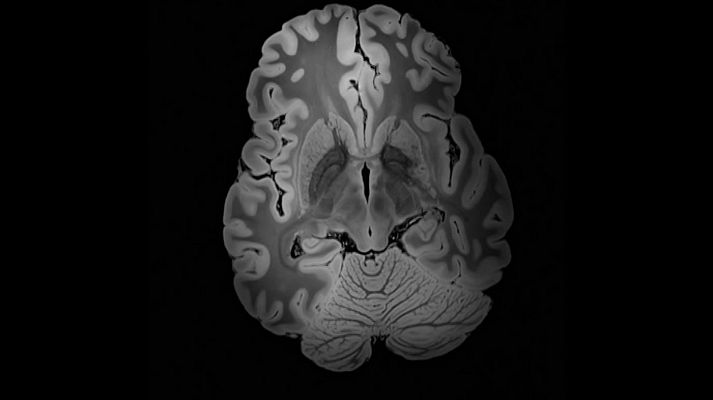

El Barcelona Beta Brain Research Center de la Fundación Pasqual Maragall es un centro dedicado a la investigación del Alzheimer. Miles de personas participan en el estudio Alfa, que pretende conocer los factores de riesgo y los indicadores biológicos que podrían incidir en el desarrollo de ésta enfermedad. Entrevistamos a Jordi Camí, director de la Fundación Pascual Maragall y del Parque de Investigación Biomédica de Barcelona. En la segunda parte vemos cómo la empresa ARISTON y la Universidad de Copenhague han conseguido el reto de construir una casa climatizada en Groenlandia que facilite el trabajo de los investigadores.